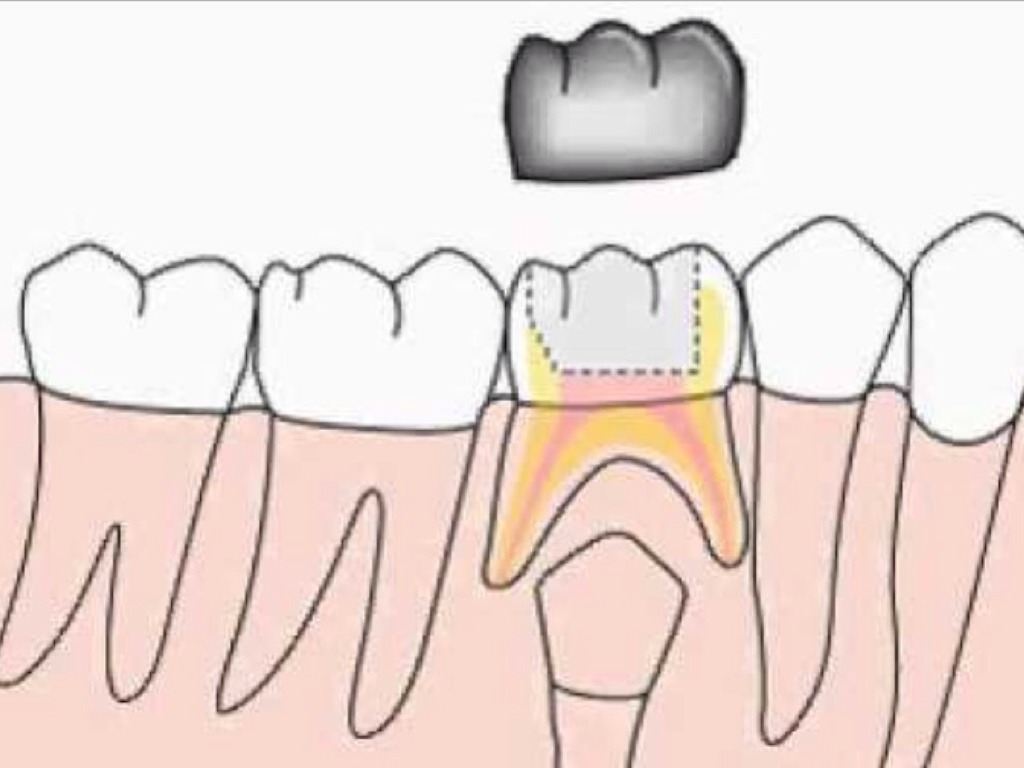

CORONAS

Untitled Slide